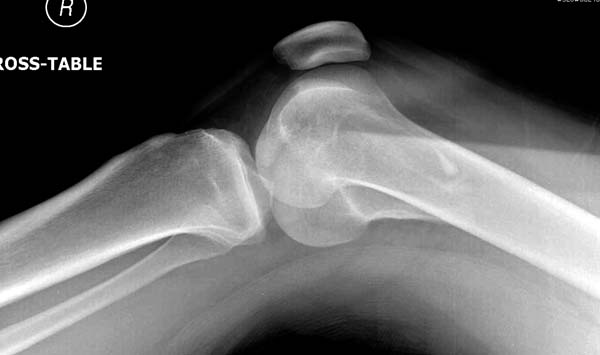

[Ortho] Нелеченный перелом Hoffa

Здесь представлены различные варианты фиксации перелома, а также снимки

комбинации перелома с повреждением хряща (12-19). Пластика хряща

OsseoFit и установка custom made plate.